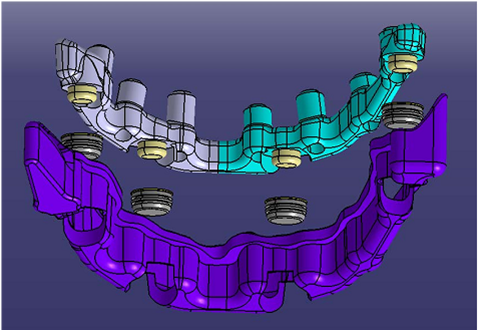

סוג השיקום הוא " קבוע נשלף" FIXED DETACHABLE.

זהו שיקום המתפקד כמו גשר קבוע יציב לחלוטין אך ניתן להסרה וניקוי בצורה יעילה כפי ששום שיקום אחר אינו מאפשר.

זהו השיקום בה' הידיעה המומלץ לבני הגיל השלישי.